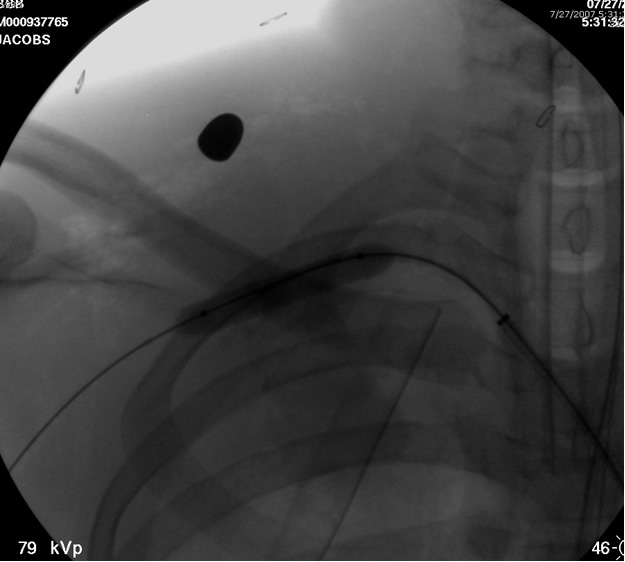

The patient is positioned supine with the ipsilateral upper extremity prepped out at a 90º angle and with both groins and chest prepped in as well. The right femoral artery is percutaneously engaged in a standard Seldinger technique with a standard short 5F sheath. We utilize an 0.035 inch hydrophilic angled Glidewire® (Terumo Medical Corporation, Somerset, NJ), which is brought up into the ascending aorta and followed with a JR4(C.R. Bard Inc. Murray Hill, NJ) catheter. The C-arm is positioned in a 25º LAO view to “open the arch” and the aortogram is commenced delineating the arch and arch vessel anatomy. Gentle traction and pullback on the catheter allows us to engage the target arch vessel, selectively advancing the Glidewire into the appropriate vessel. Next, once the wire is placed far distally the catheter is gently advanced into the appropriate vessel where selective angiograms are performed (Figure 1). Inability to traverse the transected subclavian artery may mandate a retrograde transbrachial approach.

![]() |

| Figure 2: Post deployment of angled glide wire and JR4 catheter past the transected subclavian artery revealing patent vessel distally. |